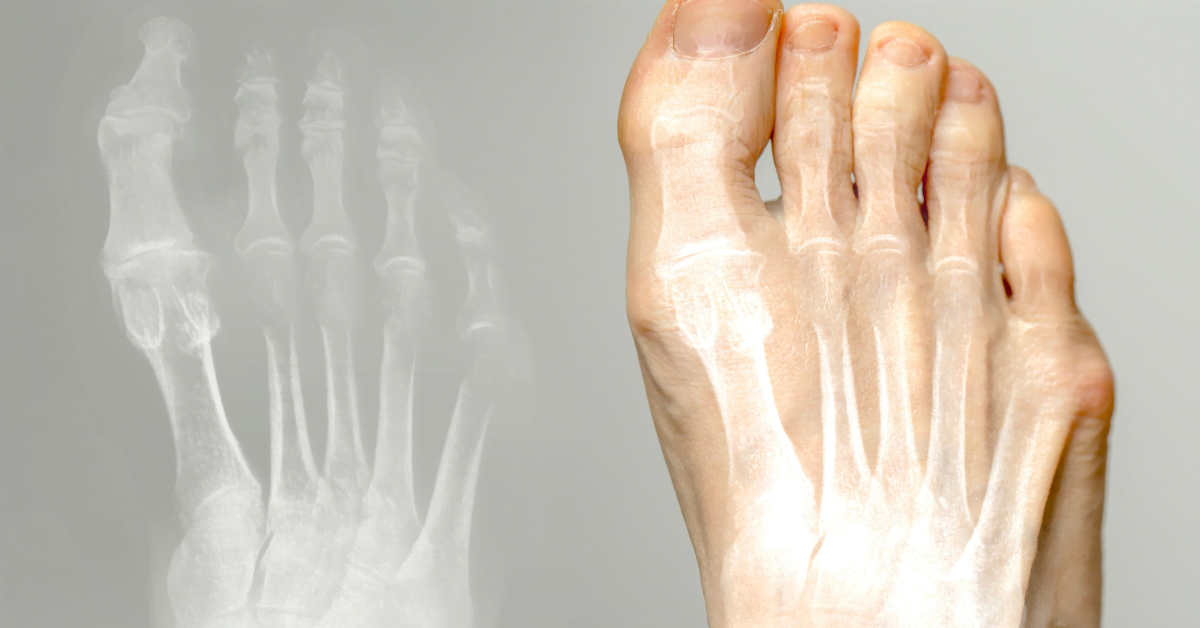

Le hallux valgus (oignon) est une affection où le gros orteil se dirige vers l'intérieur et forme une bosse à la base. Cela peut provoquer douleur et inconfort. Ici, vous trouverez les causes, le traitement et la prévention.

Le gros orteil se courbe vers les autres orteils, créant une bosse au pied. Causes : chaussures étroites, talons hauts, hérédité, pieds plats ou arthrite. De mauvaises chaussures provoquent pression et frottement, pouvant entraîner une bursite.

Hallux valgus est une déviation du gros orteil vers l'intérieur, avec une bosse à la base. Souvent causée par des chaussures étroites, des talons hauts ou l'hérédité. Peut provoquer douleur et bursite.